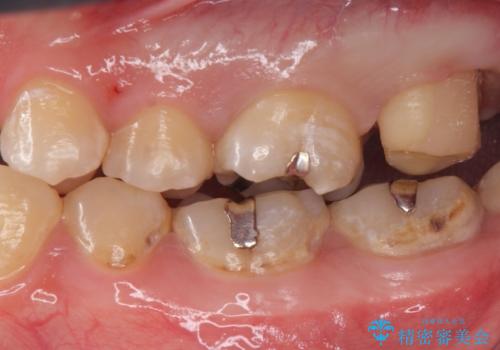

- 奥歯が欠けてしみるとのことで来院された患者様です。

かなり大きな虫歯であることと、清掃不良により歯全体が脱灰していたため、クラウンでの修復処置を行います。

奥に生えている親知らずも清掃不良であったため、今回治療する歯の清掃性を高めるために抜歯を行います。